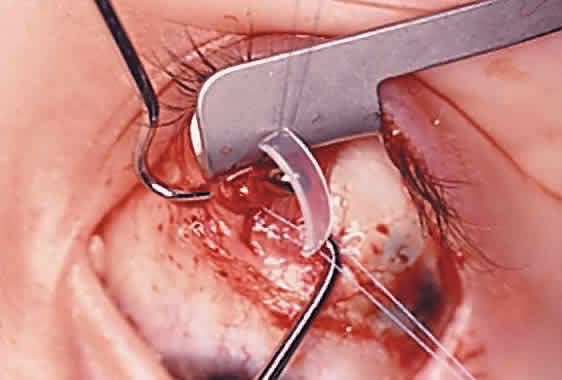

The superior oblique tendon tuck is best performed near the tendon's insertion as described by McLean.48 The surgical procedure is performed through a superior temporal cul-de-sac approach (Fig. 4). With the globe depressed, an incision is made through the conjunctiva and Tenon's fascia just temporal to the lateral border of the superior rectus muscle and parallel to the corneoscleral limbus. The superior rectus muscle is engaged on a muscle hook and the globe adducted and positioned in maximal depression. The lateral rectus muscle may also be used to assist positioning the globe. Using two small muscle hooks, the conjunctival incision is stretched open posteriorly in a triangular fashion. The lateral border of the superior rectus muscle is elevated and displaced medially. The globe is then examined for the glistening, white fibers of the superior oblique tendon running flush against the sclera and directed anteromedially. The anterior portion of the reflected tendon typically inserts under the lateral border of the superior rectus muscle, 5 to 7 mm posterior to its insertion. However, this location may vary, and anatomic anomalies are common (Fig. 5).12,37,47,48 The superior oblique tendon looks very different near its scleral insertion than 10 mm more proximally, where it becomes cordlike and enters Tenon's fascia after passing under the belly of the superior rectus muscle. Inexperienced surgeons have mistaken the lateral portion of the tendinous insertion of the superior rectus muscle for the superior oblique tendon (Fig. 6).49 However, the superior rectus muscle travels toward the orbital apex and contains prominent anterior ciliary blood vessels, whereas the superior oblique tendon is directed toward the trochlea and is usually avascular. In addition, direct traction on the superior oblique tendon can easily be palpated at the trochlea by pressing a finger over the eyelid in the superior nasal quadrant of the orbit.10 This is a reliable sign that the tendon (and not some other structure) has been engaged on the muscle hook.

After the superior oblique tendon has been positively identified, it is gathered on a Stevens tenotomy or other muscle hook with a small tip. This maneuver is most readily accomplished by passing the hook over the tendon with its tip parallel to the sclera and pointed medially. Direct visualization of the tendon is essential, in that blind sweeping can be hazardous. A superior temporal vortex vein usually exists near the posterior insertion of the superior oblique tendon and the optic nerve is within reach. In addition, it is important to avoid passing the muscle hook into orbital fat because its release into the sub-Tenon's space predisposes the eye to develop an adherence syndrome postoperatively.50

The superior oblique tendon is drawn forward through the surgical wound and attachments to Tenon's fascia and the superior rectus muscle are cut. A second pass of the muscle hook helps ensure that no fibers have been missed. Gross assessment of tendon laxity is then performed. A lax tendon requires a greater amount of tuck, whereas a normal tendon should be approached with caution, and a taut tendon should not be shortened at all. A Bishop tendon tucker is helpful to control the isolated tendon and permits the surgeon to quantitate the amount of tendon shortening conveniently. The tendon is drawn in the tucker until snug, but not tight. The loop of tendon is then sewn to itself using a nonabsorbable suture such as 5-0 braided Dacron. After this provisional tuck has been completed, the tendon is released into the orbit and a traction test is performed with the eye positioned in maximum adduction. It has been our experience that the ideal tuck results when the amount of tendon shortening produces its first resistance to elevation as the inferior limbus crosses an imaginary line between the medial and lateral canthus (Fig. 7).34,51 Care must be taken not to retropulse the globe into the orbit, because this exaggerates the duction limitation. An average tendon shortening of approximately 12 mm is required in congenital superior oblique muscle palsy (lax tendon) and 8 mm in acquired palsy (normal tendon). However, the optimum amount of tuck does not necessarily correlate with the size of the hypertropia in primary gaze position and intraoperative titration is essential. If the initial tuck is too tight or too loose based on results of traction testing, the tendon is retrieved from the orbit and the tuck is adjusted. The final tie-off is performed by passing the suture through and around the superior oblique tendon a second time after which it is tied securely. This minimizes the potential for tendon slippage through the tuck and provides additional security should a suture loop fail postoperatively. It is not necessary to sew the redundant tendon to the sclera. Conjunctival closure is performed at the surgeon's discretion. A running suture of 6-0 plain catgut is well tolerated and prevents the conjunctiva from gaping open postoperatively.